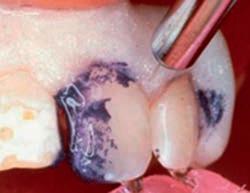

Sable Seek caries indicator contains FD&C dyes, and Seek caries indicator contains D&C dyes in a glycol base. Both are used to stain carious and demineralized dentin.

Seek and Sable Seek caries indicators stain carious and demineralized dentin and can be very useful for difficult-to-see areas, for example; undercuts of preparations, dark dentin, areas along the DE junction, etc. Green Sable Seek caries indicator helps visualization of decay in deep caries cases to help avoid pulp exposures.

PROCEDURE

dentin) with slow-speed round bur or excavator. To control overexcavating near the pulp, remove final portion of caries with hand excavator.